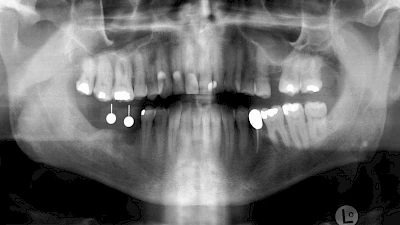

Implantate sind künstliche Zahnwurzeln. Nach einer gewissen Einheilzeit im Knochen (meist 3-6 Monate) erfolgt über einen separaten Aufbau (Abutment) die Befestigung einer Krone bzw. Brücke oder Zahnprothese.

In diesen Fällen kann die Planung mittels verschieden aufwendiger Röntgen-Techniken (Übersichtsaufnahme, DVT) ggf. unter Zuhilfenahme speziell angefertigter Planungsschablonen sinnvoll sein.